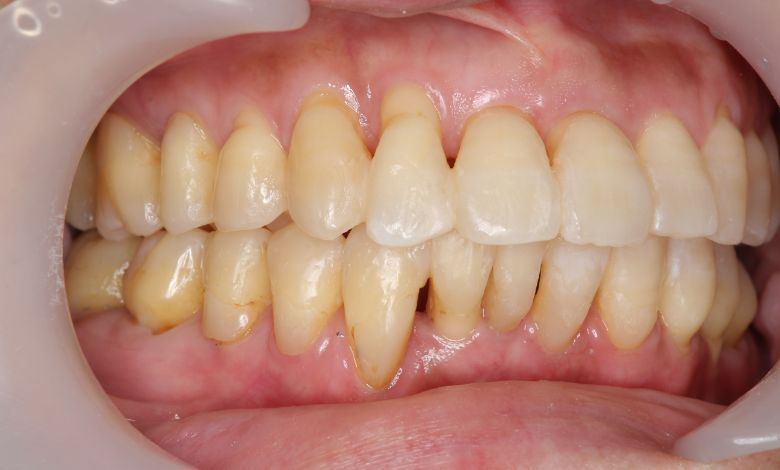

正常な咬合関係が確立され、前歯の自然なアーチと歯軸も整い、歯列全体が滑らかなカーブを描く美しい歯並びに

上下ともに歯並びが乱れており、噛み合わせにも大きな不調和が見られる

上下の歯がしっかりと噛み合う、美しい咬合(こうごう)が得られた

精密検査の結果、当院では抜歯を行わず、歯列弓の拡大によってスペースを確保し、非抜歯での矯正治療を選択しました。歯列の叢生(ガタガタ)は解消され、機能的かつ審美的に優れた咬合が得られました。